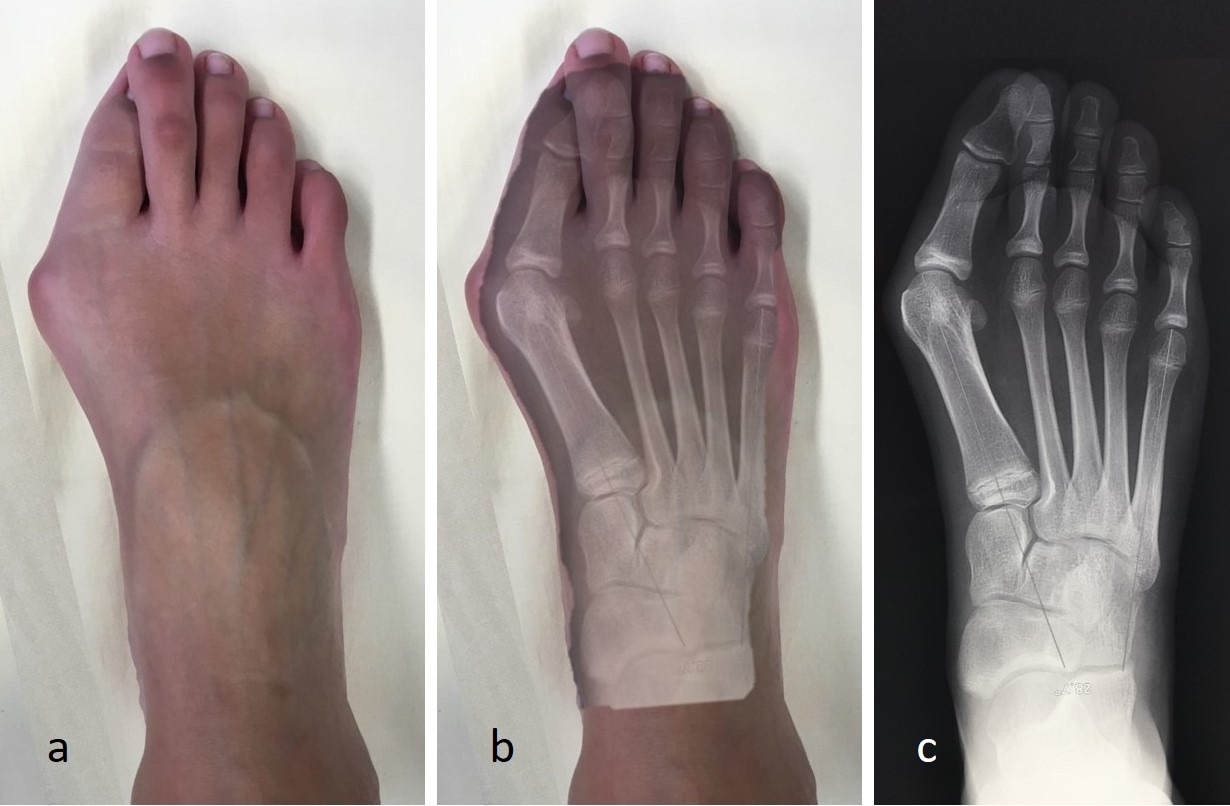

L’Hallux Valgus est la pathologie la plus fréquente de l’avant-pied. Il se caractérise par une déviation du gros orteil (l’hallux) vers l’extérieur, qui s’accompagne d’une proéminence osseuse sur le bord interne du pied : l’exostose, communément appelée « oignon ».

Cette bosse entre en conflit avec la chaussure, créant une inflammation d’une petite poche de liquide (la bourse séreuse) située sous la peau : c’est la bursite, responsable de rougeurs, de chaleur et de vives douleurs.

L’Hallux Valgus est une pathologie évolutive. Au départ, la gêne est esthétique ou liée au frottement. Mais avec le temps, la déviation du gros orteil entraîne une désorganisation de tout l’avant-pied :

1. Perte d’appui : Le gros orteil ne joue plus son rôle de propulseur.

2. Transfert de charge : Le poids du corps se reporte sur les 2ème et 3ème orteils, créant des douleurs sous la plante du pied (métatarsalgies) et des durillons.

3. Griffes d’orteils : Le 2ème orteil, poussé par le premier, se replie en « marteau » ou en « griffe ».